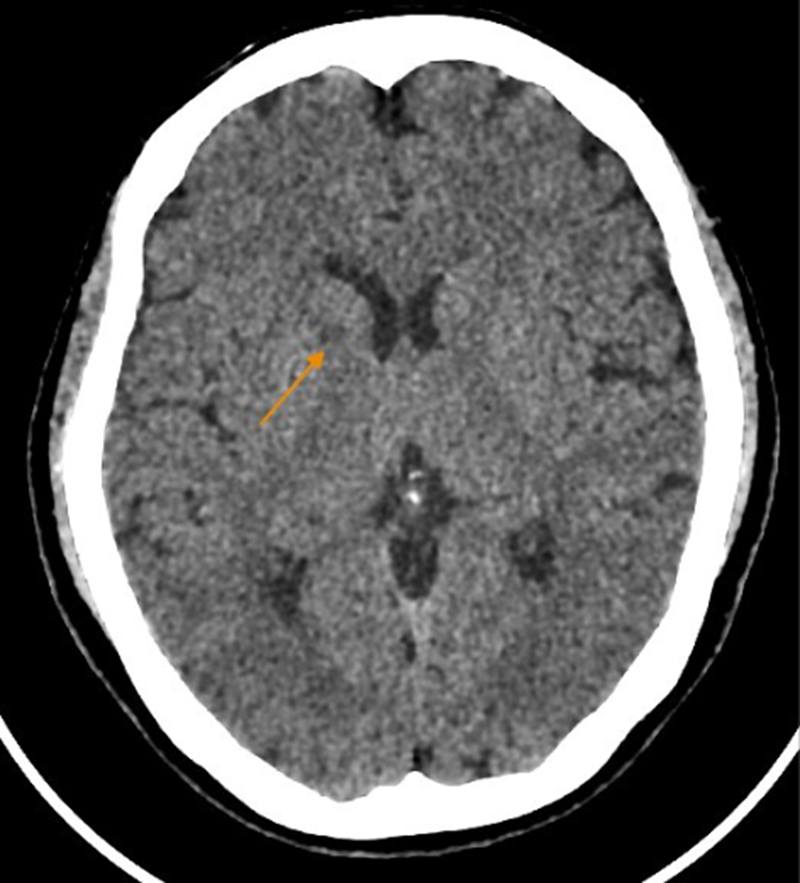

Khi sự việc xảy ra, kết quả thăm khám cho thấy bệnh nhân huyết áp tăng 150/90 mmHg, cơ lực nửa người trái giảm rõ, nếp mũi má mờ, méo miệng, phản xạ gân xương giảm. Chụp cắt lớp vi tính sọ não ghi nhận xơ vữa vôi hóa động mạch cảnh trong hai bên đoạn xoang hang và động mạch đốt sống. X-quang tim – phổi cho thấy cung động mạch chủ giãn nhẹ kèm vôi hóa. Siêu âm Doppler mạch cảnh phát hiện mảng xơ vữa vôi hóa tại xoang cảnh trái; siêu âm tim cho thấy hở nhẹ van động mạch chủ.